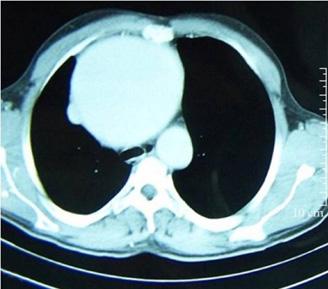

TAC tórax: identifica neumotórax ocultos (↑sensibilidad y especificidad)

Figura 18. Neumotórax a tensión derecho Es evidente el desplazamiento marcado de las estructuras cardiomediastínicas hacia el hemitórax izquierdo.